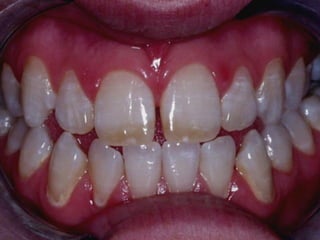

Cualquier lesión

de caries

En cualquier

diente

menor de 6 años

Caries de

Niñez

¿y cuando Temprana

es muy    Severa

extensa?

Para clasificarla

como  severa

hay que cumplir

ciertos criterios

Menor de 3 años con

cualquier evidencia

de caries en

superficie lisa

3, 4, 5 años con

superficie lisa de

incisivo central

Cantidad total de

superficies afectadas es

≥de 4 a los 3 años, 5 a los 4

y 6 a los 5

Las primeras lesiones no son cavitadas

a medida que pasan los años

aparecen más lesiones cavitadas